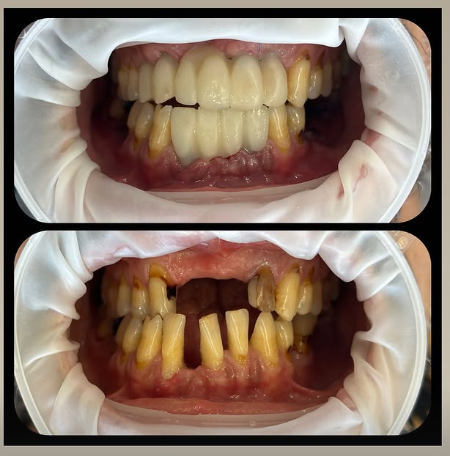

ایمپلنت یک روزه در مشهد (ایمپلنت فوری در مشهد) روشی نوین و پیشرفته در دندانپزشکی است که امکان کاشت دندان در یک روز را بدون درد و با ماندگاری بالا فراهم میکند. در این روش، برخلاف ایمپلنتهای سنتی که نیاز به چندین ماه انتظار برای جوش خوردن پایه با استخوان فک دارند، دندان جدید در همان روز جایگذاری میشود و بیمار میتواند بلافاصله از لبخندی زیبا و طبیعی لذت ببرد. استفاده از فناوریهای مدرن، مواد باکیفیت و تکنیکهای دقیق جراحی در این روش، باعث شده است که افراد بیشتری به جایگزینی سریع و موثر دندانهای ازدسترفته خود با ایمپلنتهای یکروزه روی آورند.

در ابتدا به بررسی تعریف ایمپلنت یک روزه در مشهد و تفاوت آن با روشهای سنتی کاشت دندان میپردازیم. ایمپلنت یک روزه در مشهد یا ایمپلنت فوری در مشهد، روشی نوین در دندانپزشکی است که به بیمار این امکان را میدهد تا در یک روز دندان ازدسترفته خود را جایگزین کند، بدون اینکه نیاز به ماهها انتظار برای جوش خوردن ایمپلنت به استخوان فک باشد. در این روش، پس از قرار دادن پایه تیتانیومی در فک، یک روکش موقت روی آن نصب میشود تا بیمار بتواند بلافاصله از دندان جایگزینشده استفاده کند.

ایمپلنت فوری در مشهد (ایمپلنت یک روزه در مشهد) با روشهای سنتی ایمپلنت دندان تفاوتهای قابل توجهی دارد. در روش سنتی، پس از کشیدن دندان، معمولاً باید چند ماه صبر کرد تا بافت استخوان فک بهبود یابد و سپس فرایند کاشت ایمپلنت آغاز شود، که خود این مرحله هم چند ماه تا جایگیری نهایی طول میکشد. در روش ایمپلنت فوری در مشهد، پایه تیتانیومی ایمپلنت بلافاصله بعد از کشیدن دندان درون استخوان فک قرار میگیرد و در بسیاری از موارد، تاج موقت نیز در همان جلسه نصب میشود. این روش زمان درمان را بهطور چشمگیری کاهش میدهد و به حفظ ساختار طبیعی لثه و استخوان فک نیز کمک میکند.

ایمپلنت فوری در مشهد به دلیل سرعت بالا، کاهش تعداد جلسات درمانی و امکان جایگزینی دندان در یک روز، گزینهای جذاب برای بسیاری از بیماران است. این روش علاوه بر بهبود زیبایی لبخند در کوتاهترین زمان، از تحلیل رفتن استخوان فک جلوگیری کرده و بیمار را از دورههای طولانی انتظار و جراحیهای متعدد بینیاز میکند. همچنین، ایمپلنت یک روزه در مشهد با کاهش نیاز به بخیه و جراحی گسترده، تجربهای راحتتر و کمدردتر را برای بیماران فراهم میآورد.